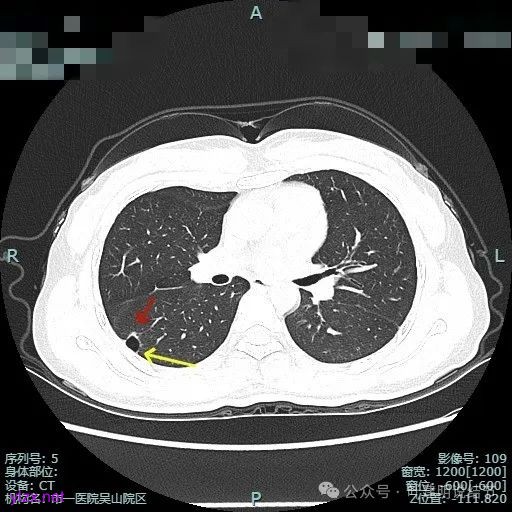

囊壁局部较厚,但囊壁内也是有小空泡的,病灶贴着胸膜。

病灶部分囊壁是混合磨玻璃成分的,整体轮廓较清。

边缘区也有偏实性成分,磨玻璃成分也还是明显的,有微小血管进入。